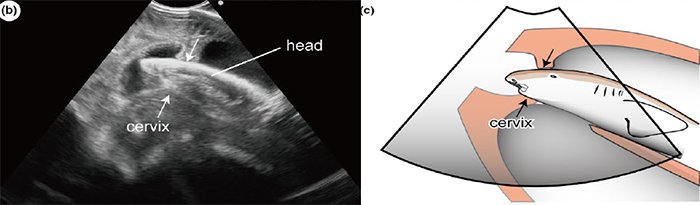

Специалисты океанариума Тюрауми, Япония, зафиксировали частую миграцию эмбрионов между правой и левой матками обследываемых акул. Открытие удалось сделать благодаря новому ультразвуковому оборудованию, предназначенному для сканирования человеческой беременности и приспособленному под акул так, что оно способно быть устойчивым к воздействию влаги и давления.

Несколько лет ученые изучали трех беременных акул. Было сделано более 40 ультразвуковых видео, на которых до четырех акулят активно двигались внутри каждой матери. У одной самки зародыши трижды поменялись местами. У второй эмбрионы оказались шустрее: было зарегистрировано 24 миграции в течение всей беременности. На одном из снимков видно, как произошел фактический обмен матками, а один из эмбрионов быстро продвигался от одной матки к другой. Скорость его равнялась восьми сантиметрам в секунду, что очень удивило исследователей.

Эмбрионы акулы. © Ethology